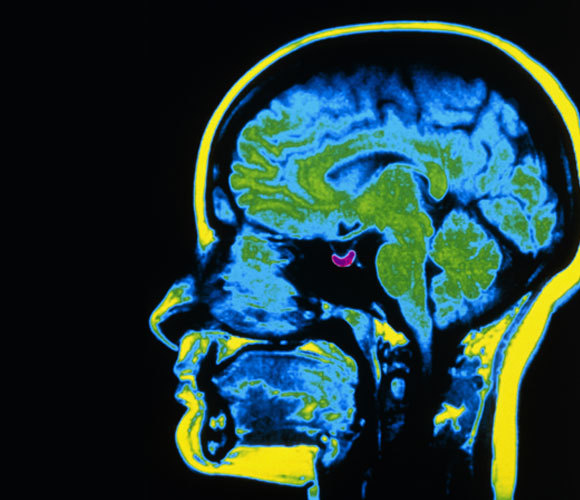

החוקרים הראו על סמך סריקות MRI שהגודל הממוצע של בלוטת יותרת המוח משתנה במחזוריות שנתית. צילום MRI עם בלוטת יותרת המוח מודגשת בסגול | Scott Camazine, Science Source, Science Photo Library

על פי המודל, הגדילה וההתכווצות של הבלוטות היא תהליך איטי שנמשך כמה חודשים, כך שמחזור שלם שלו נמשך בערך שנה. אם ההשערה הזאת נכונה, הרי שגודלה של בלוטת יותרת המוח אמור להשתנות לאורך השנה. ואכן החוקרים הראו על סמך ניתוח של סריקות MRI שהגודל הממוצע של בלוטת יותרת המוח משתנה במחזוריות שנתית – היא גדולה יותר בקיץ וקטנה בחורף.